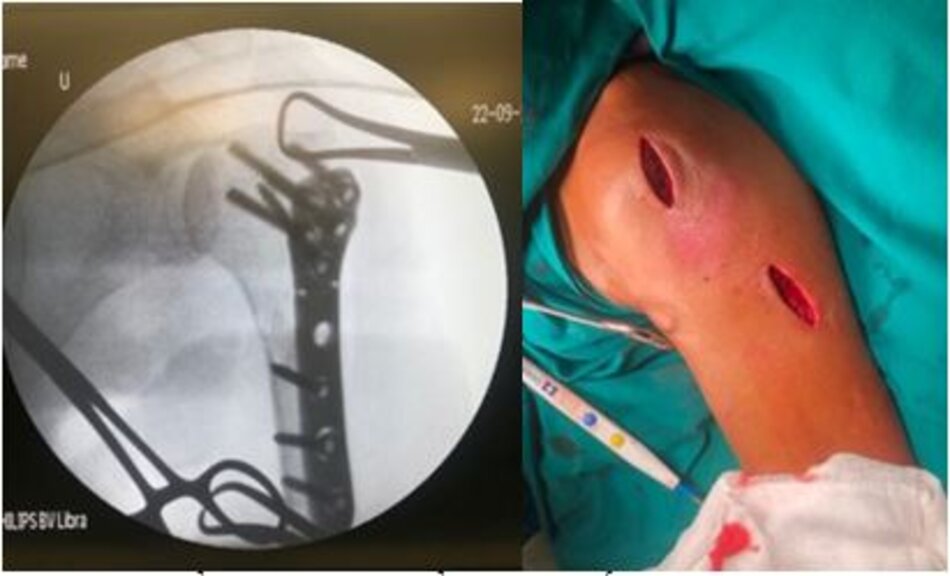

Phẫu thuật Đinh nội tuỷ Gamma không mở ổ gãy dưới màn tăng sáng điều trị gãy liên mấu chuyển xương đùi

Phẫu thuật Đinh nội tuỷ Gamma

Đường mổ đóng đinh kín không mở ổ gãy

Phim Xquang sau mổ đóng đinh kín